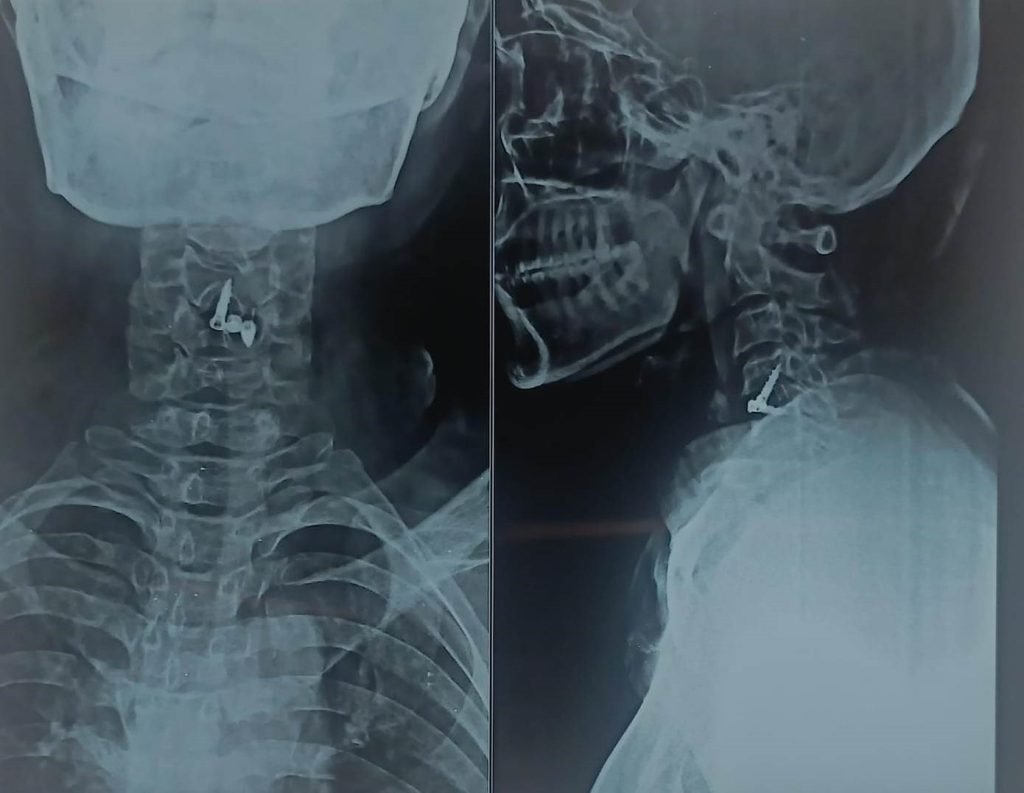

Diagnosis

Dr. Nitish Agrawal ensures accurate diagnosis through:

- MRI of the cervical spine (most important investigation)

- X-rays or CT scan to assess spinal alignment and bone changes

- Anterior Cervical Discectomy and Fusion (ACDF)

- Cervical decompression with titanium spacer, plate, and screws